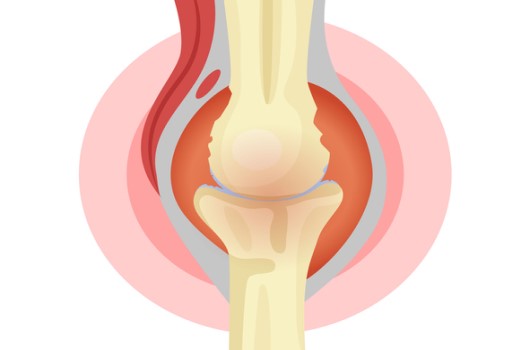

콘드로이친황산은 관절과 연골 등에 존재하는 생리활성물질로서 관절 · 연골에 영양을 공급하며 연골 분해 효소를 제한하고 새로운 연골 형성을 촉진하 다고 알려져 있어요 류머티즘학회 유럽연합(EULAR)에서는 2003년에 이미 무릎 골관절염 치료를 위해 콘드로이친황산을 섭취할 것을 강력하게 권고한 바 있어요.

콘드로이친 효능 8. 골관절염

콘드로이친은 보통 골관절염 증상 관리를 위한 치료제로 사용되고 있어요. 미국에서 시행된 골관절염 환자 604명을 대상으로 한 연구에서 콘드로이친의 골관절염 통증에 대한 효과를 관찰했는데 그 결과, 무릎 골관절염 통증이 있는 사람들의 약 10%가 콘드로이친으로 인한 통증완화와 개선효과를 체험했다고 밝혔어요.

콘드로이친은 관절세포를 재생시키는데 도움을 주고 외부 충격을 흡수, 개선시키는데에도 뛰어난 효과가 있어요. 그러나 콘드로이친은 노화가 진행되면서 수치가 점점 저하돼요. 이는 곧 연골의 뼈와 뼈사이의 완충효과 또는 보호기능 약화로 이어지는 것을 의미하기 때문에 나이가 들수록 콘드로이친을 보충해 주는 것이 좋아요.

가장 잘 알려진 효능 중 한가지는 관절염 증상을 개선하고 치료하는 데 분비된다는 것인데요. 한 연구에서 무릎 관절염이 있는 참가자는 6개월 동안 황산 콘드로이틴을 계속해서 섭취한 결과 관절염 통증이 개선된 것으로 나타났어요

콘드로이친은 연골을 재생 및 복구하고 무릎이 받는 충격과 스트레스를 흡수해서 연골을 보호할 수 있어요. 반대로 콘드로이친이 부족하게되면 연골은 수분 보유력과 탄력을 잃게 되고, 연골이 계속 마모되면서 뼈끼리 마찰을 일으켜 관절염을 유발하기 쉽기 때문인데요.